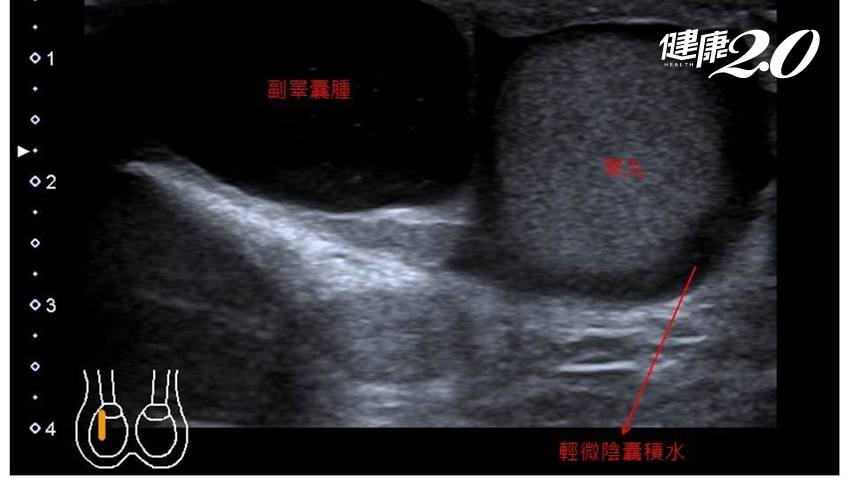

書田診所泌尿科主任醫師周固表示,患者大約3年前,自覺右側的陰囊比左側大,但是沒有任何不適,便不以為意。這次在門診中,經觸診及超音波檢查發現,患者陰囊大小約7.5公分x7公分x3公分,診斷為副睪囊腫合併陰囊水腫,建議先暫停激烈運動,穿著寬鬆衣物,倘陰囊有摩擦破皮使用外用藥物防止感染,疫情和緩後以手術治療。

造成陰囊腫大的可能原因有:副睪囊腫、睪丸腫瘤、睪丸和副睪丸發炎、陰囊水腫。此次的個案是因副睪囊腫引起陰囊腫大。副睪囊腫的發生原因,目前推測可能與感染或創傷有關,多發生於40歲以上男性,觸診時可摸到腫塊,超音波及透光檢查可見透明水囊。

▲從影像中,可看到副睪囊腫合併陰囊水腫的情況。